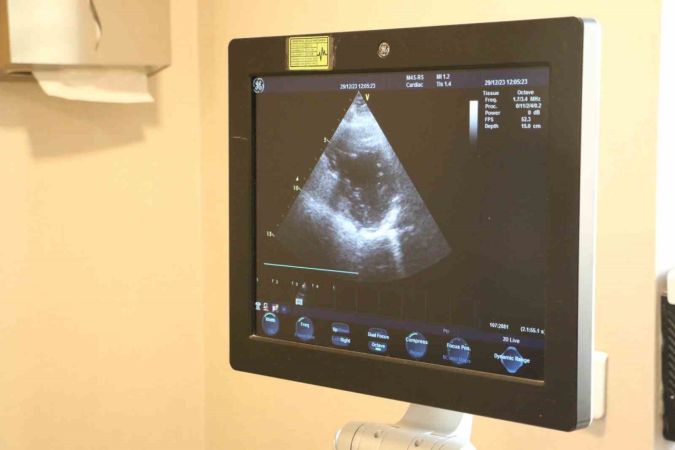

Dr. Hüseyin Akçalı, kalp kapak hastalıklarının belirtilerini detaylıca açıklıyor. Bu belirtiler arasında en dikkat çekici olanı, ayaklarda görülen şişliktir. Erken tanı ve düzenli takibin bu hastalığın yönetiminde kritik bir öneme sahip olduğu vurgulanıyor.